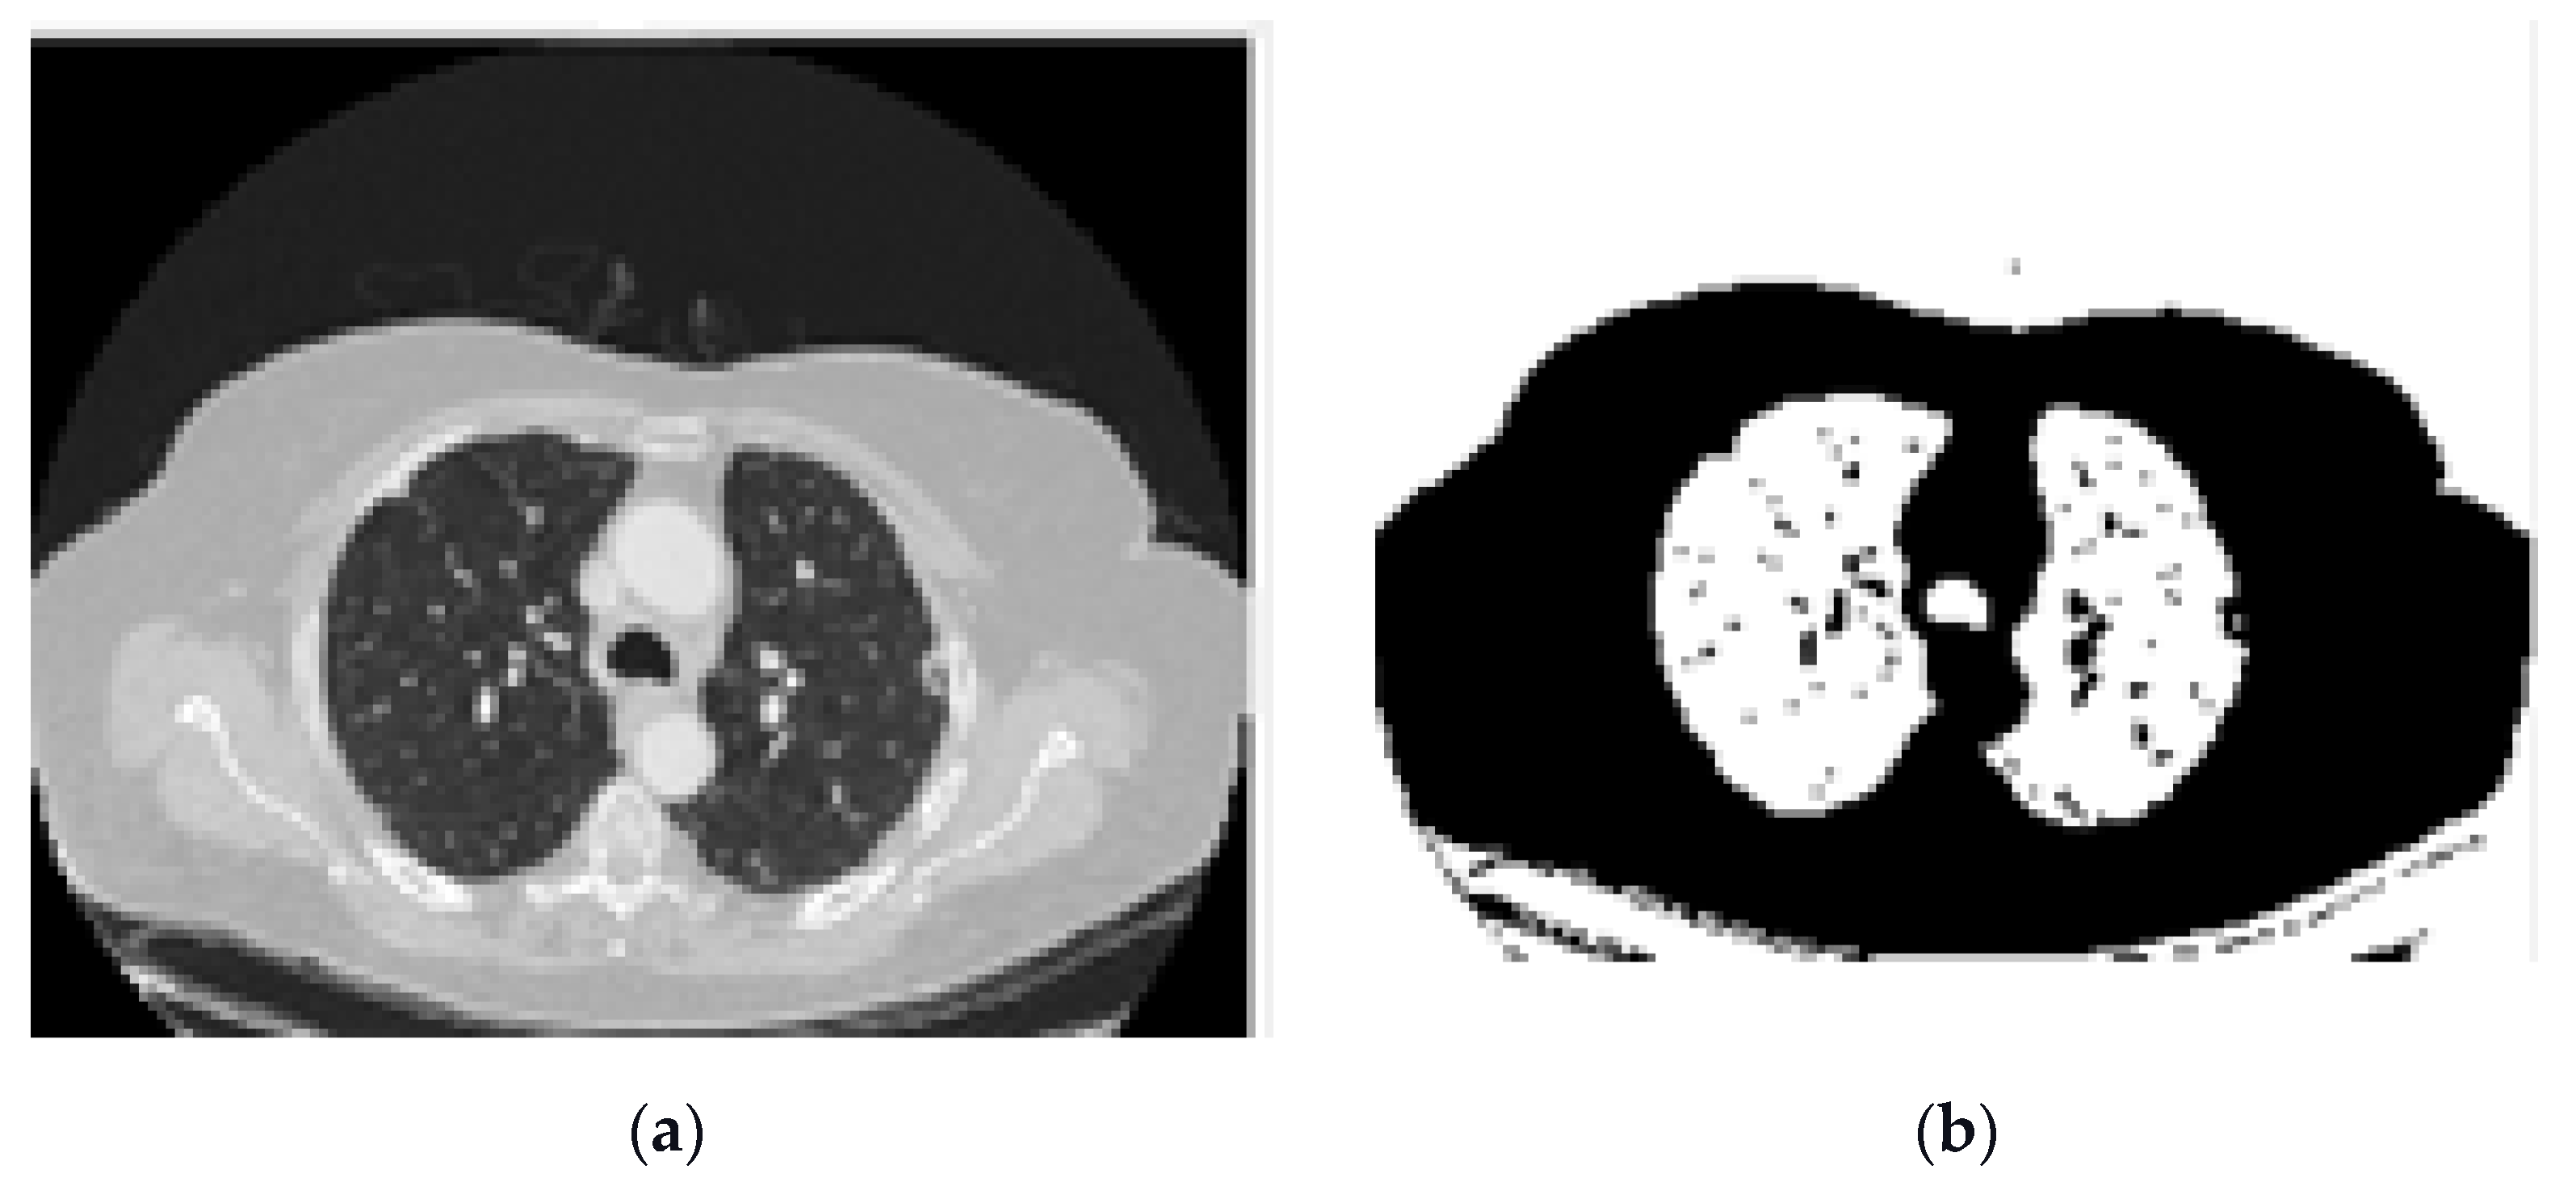

- Image binarization: In this process, a binary image is created with two values on the grey surface, i.e., black and white. The lung region poses a black colour with the value zero. Figure 8 shows the binarization process of a CT image.

- Dilation morphological operation: Morphological operations, typically applied to binary images, are used to extract and describe the geometry of the object in the image [49,50]. As a result of the binarization process described before, there would still be remaining regions of white colour around the lungs regarded as unwanted noise. Thus, morphological operations can be used to remove these regions. Moreover, there could still be some small black holes in the lung’s region, suspicious of noise caused by the binarization process. These holes should be also removed using morphological operations.